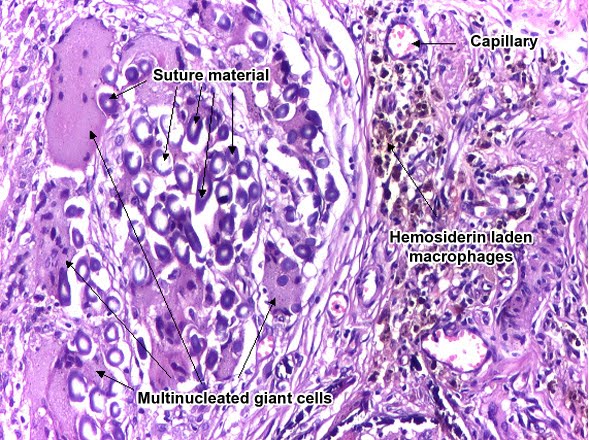

A foreign-body response to talc (talcosis) due to intravenous drug use. H&E stain.

The foreign body granuloma is a response of biological tissue to any foreign material in the tissue.[1] Tissue-encapsulation of an implant is part of this. An infection around a splinter is part of this, too.[2]

The presence of the implant changes the healing response, and this is called the foreign-body reaction (FBR). FBR consists of: protein adsorption, macrophages, multinucleated foreign body giant cells (macrophage fusion), fibroblasts, and angiogenesis.

- for·eign bod·y gran·u·lo·ma a granuloma caused by the presence of foreign particulate material in tissue, characterized by a histiocytic reaction with foreign body giant cells. foreign body granuloma Etymology: OFr, forain + AS, ...